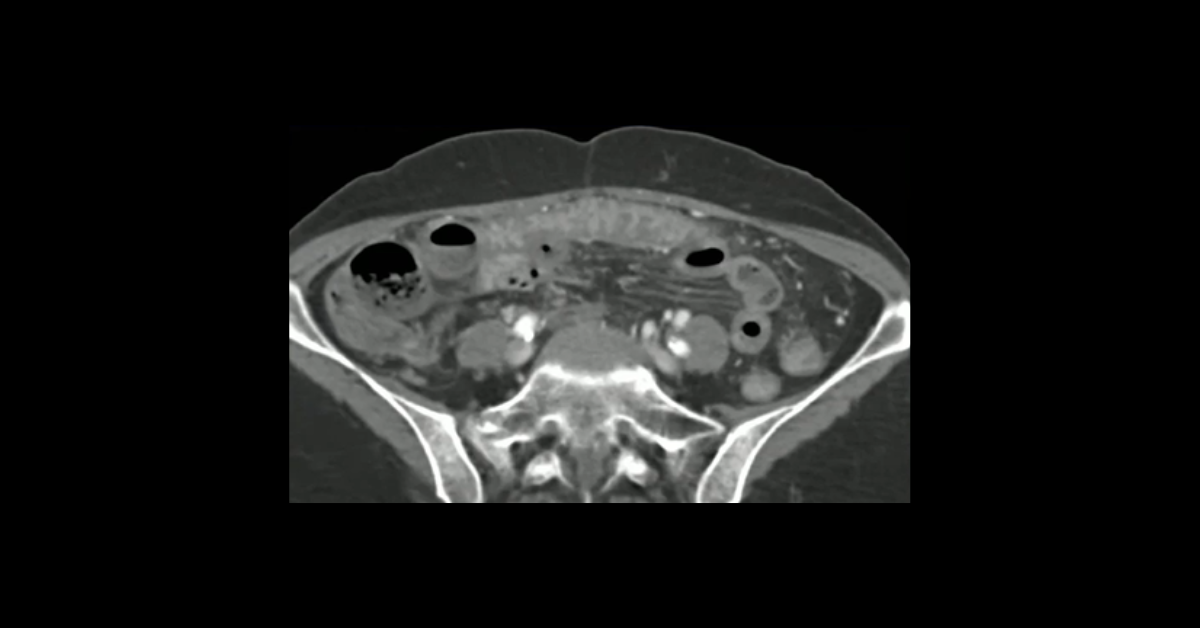

Presented by Vincent Mellnick, MD at Practical Radiology 2025. This talk will focus on common (and less common) causes of small bowel wall thickening, obstruction, and hemorrhage. The talk emphasizes the need to examine the bowel wall, contour, and contents in conjunction with clinical history in order to provide an appropriate differential diagnosis and better aid our referring clinicians.

1. Utilize plain film, CT and MRI to identify and characterize acute conditions of the small bowel

2. Identify conditions of the small bowel that result in obstruction, ischemia, inflammation, and hemorrhage

3. Differentiate between surgical and nonsurgical causes of acute small bowel pathology